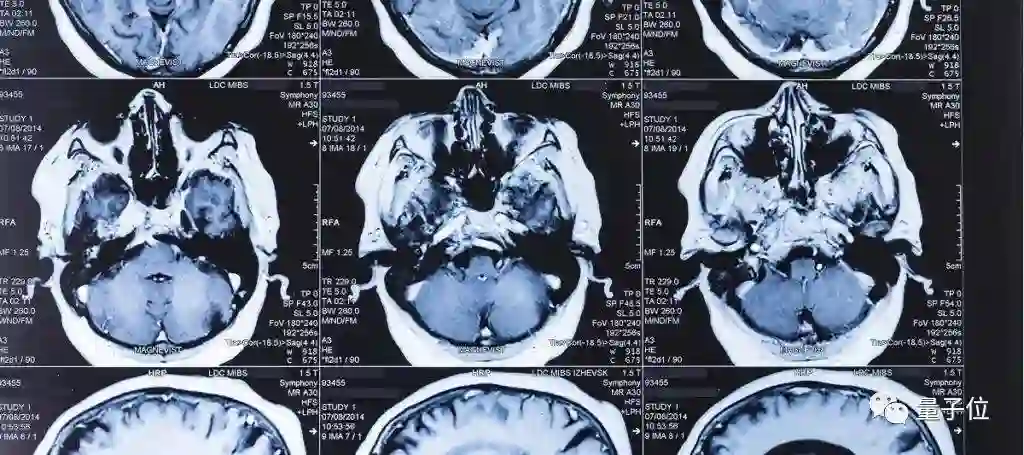

医学专家提供的图像标注是AI诊断学习的材料。目前,各大科技巨头和政府投资图像标注事业,并把数据集公开提供给其他研究人员。

样本需要专家的标注,如果样本没有任何标注,我们不知道这是一个来自健康人还是病人的样本……这是很重要的一步。——阿里云机器智能首席科学家 闵万里

国际上,谷歌的DeepMind与眼科医院Moorfield合作,用AI探查眼部疾病,目前,一个AI能够诊断出50多种眼疾,准确度达到94%。

在国内,依图科技也在进行人工智能诊断,据报道,目前依图背后的医生团队已经有400多人,为其收集的医疗数据打标签。